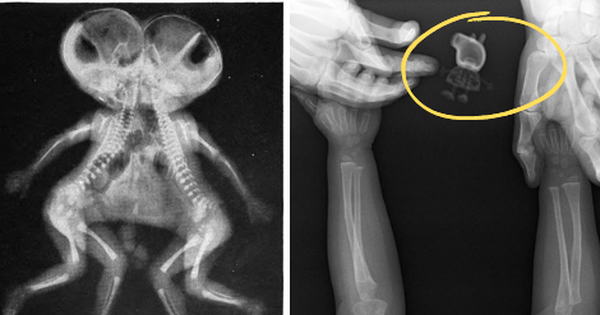

Kỹ thuật chụp X quang là một trong những phát minh vĩ đại của loài người và thực sự có ích trong ngành y học. Đặc biệt trong các trường hợp như trẻ em nuốt phải đồ vật hay những khi các chú chó nuốt rất nhiều thứ lạ đời vào bụng. Dưới đây là những tấm phim kết quả chụp X quang khá thú vị để thử khả năng đoán hình của bạn!

Hình chụp X quang của một cặp sinh đôi bị dính thân

Đứa trẻ không cho chụp X quang nếu không có mẹ và đồ chơi bên cạnh